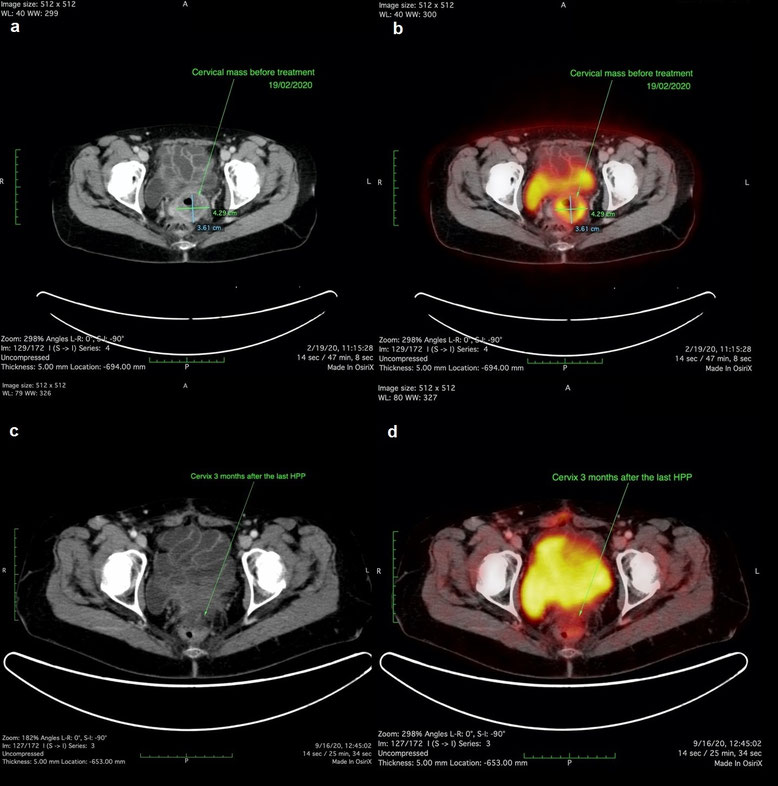

Die Patientin wurde im Februar 2020 mit wiederkehrenden vaginalen Blutungen in unserer Klinik vorstellig. Ein CT des Abdomens und Beckens und ein FDG PET-CT, welche im Februar 2020 durchgeführt wurden, bestätigten eine hoch metabolische zervikale Läsion von 3,61 x 4,29 cm Größe. Die Patientin entschied sich die regionale Chemotherapie mit HPP fortzusetzen.

Wir führten die HPP mit 50 mg Cisplatin, 30 mg Adriamycin und 15 mg Mitomycin jeweils im März und April 2020 durch. Die Vaginalblutungen stoppten zu Beginn des zweiten Zyklus. Das im Mai 2020 durchgeführte CT des Abdomens und Beckens zeigte eine 2,90 x 3,24 cm große verbliebene zervikale Läsion.

Die Patientin erhielt im Juni 2020 eine weitere isolierte Beckenperfusion. Über systemische Toxizität wurde nie berichtet.

Das im September 2020 durchgeführte FDG PET-CT zeigte keine auffällige Stoffwechselaktivität.

CT- und PET-CT-Aufnahmen einer Patientin mit Zervixkarzinom vor und nach HPP-Behandlung, zeigend Tumorreduktion und fehlende metabolische Aktivität drei Monate nach Therapieabschluss.